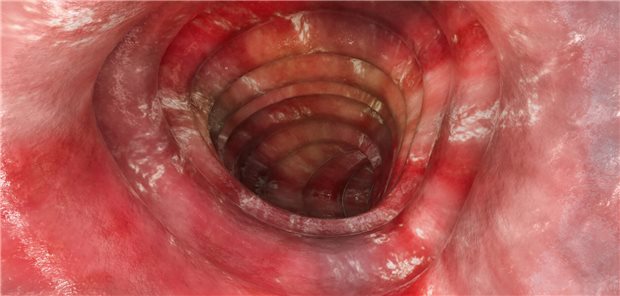

Was genau machen eigentlich endoskopisch tätige Ärzte, wenn sie Polypen und Läsionen aus Dickdarm oder Rektum entfernen? Kommt darauf an! Es werden eine Reihe verschiedener Techniken praktiziert.